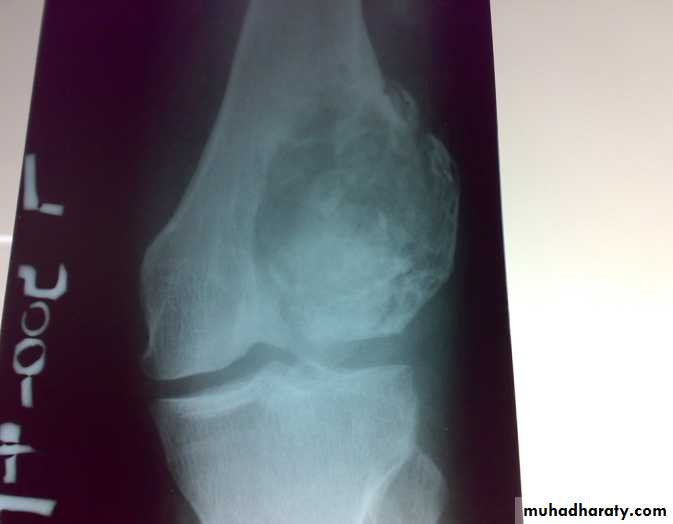

Giant cell tumor

This disease characterized by presence of giant multinucleated cells which seen in large number. The tumor cell is the stromal spindle shape cell.

The tumor is soft and friable occupying the cavity which extend to subchondral region.

Patient presented by local pain and swelling or pathological fractures. Common site is the distal femur, proximal tibia, distal radius.

X-ray show eccentric osteolytic lesion in the end of long bone ,subchondral, trabeculated (soap bubble appearance). The cortex is thin, expanded or even perforated.